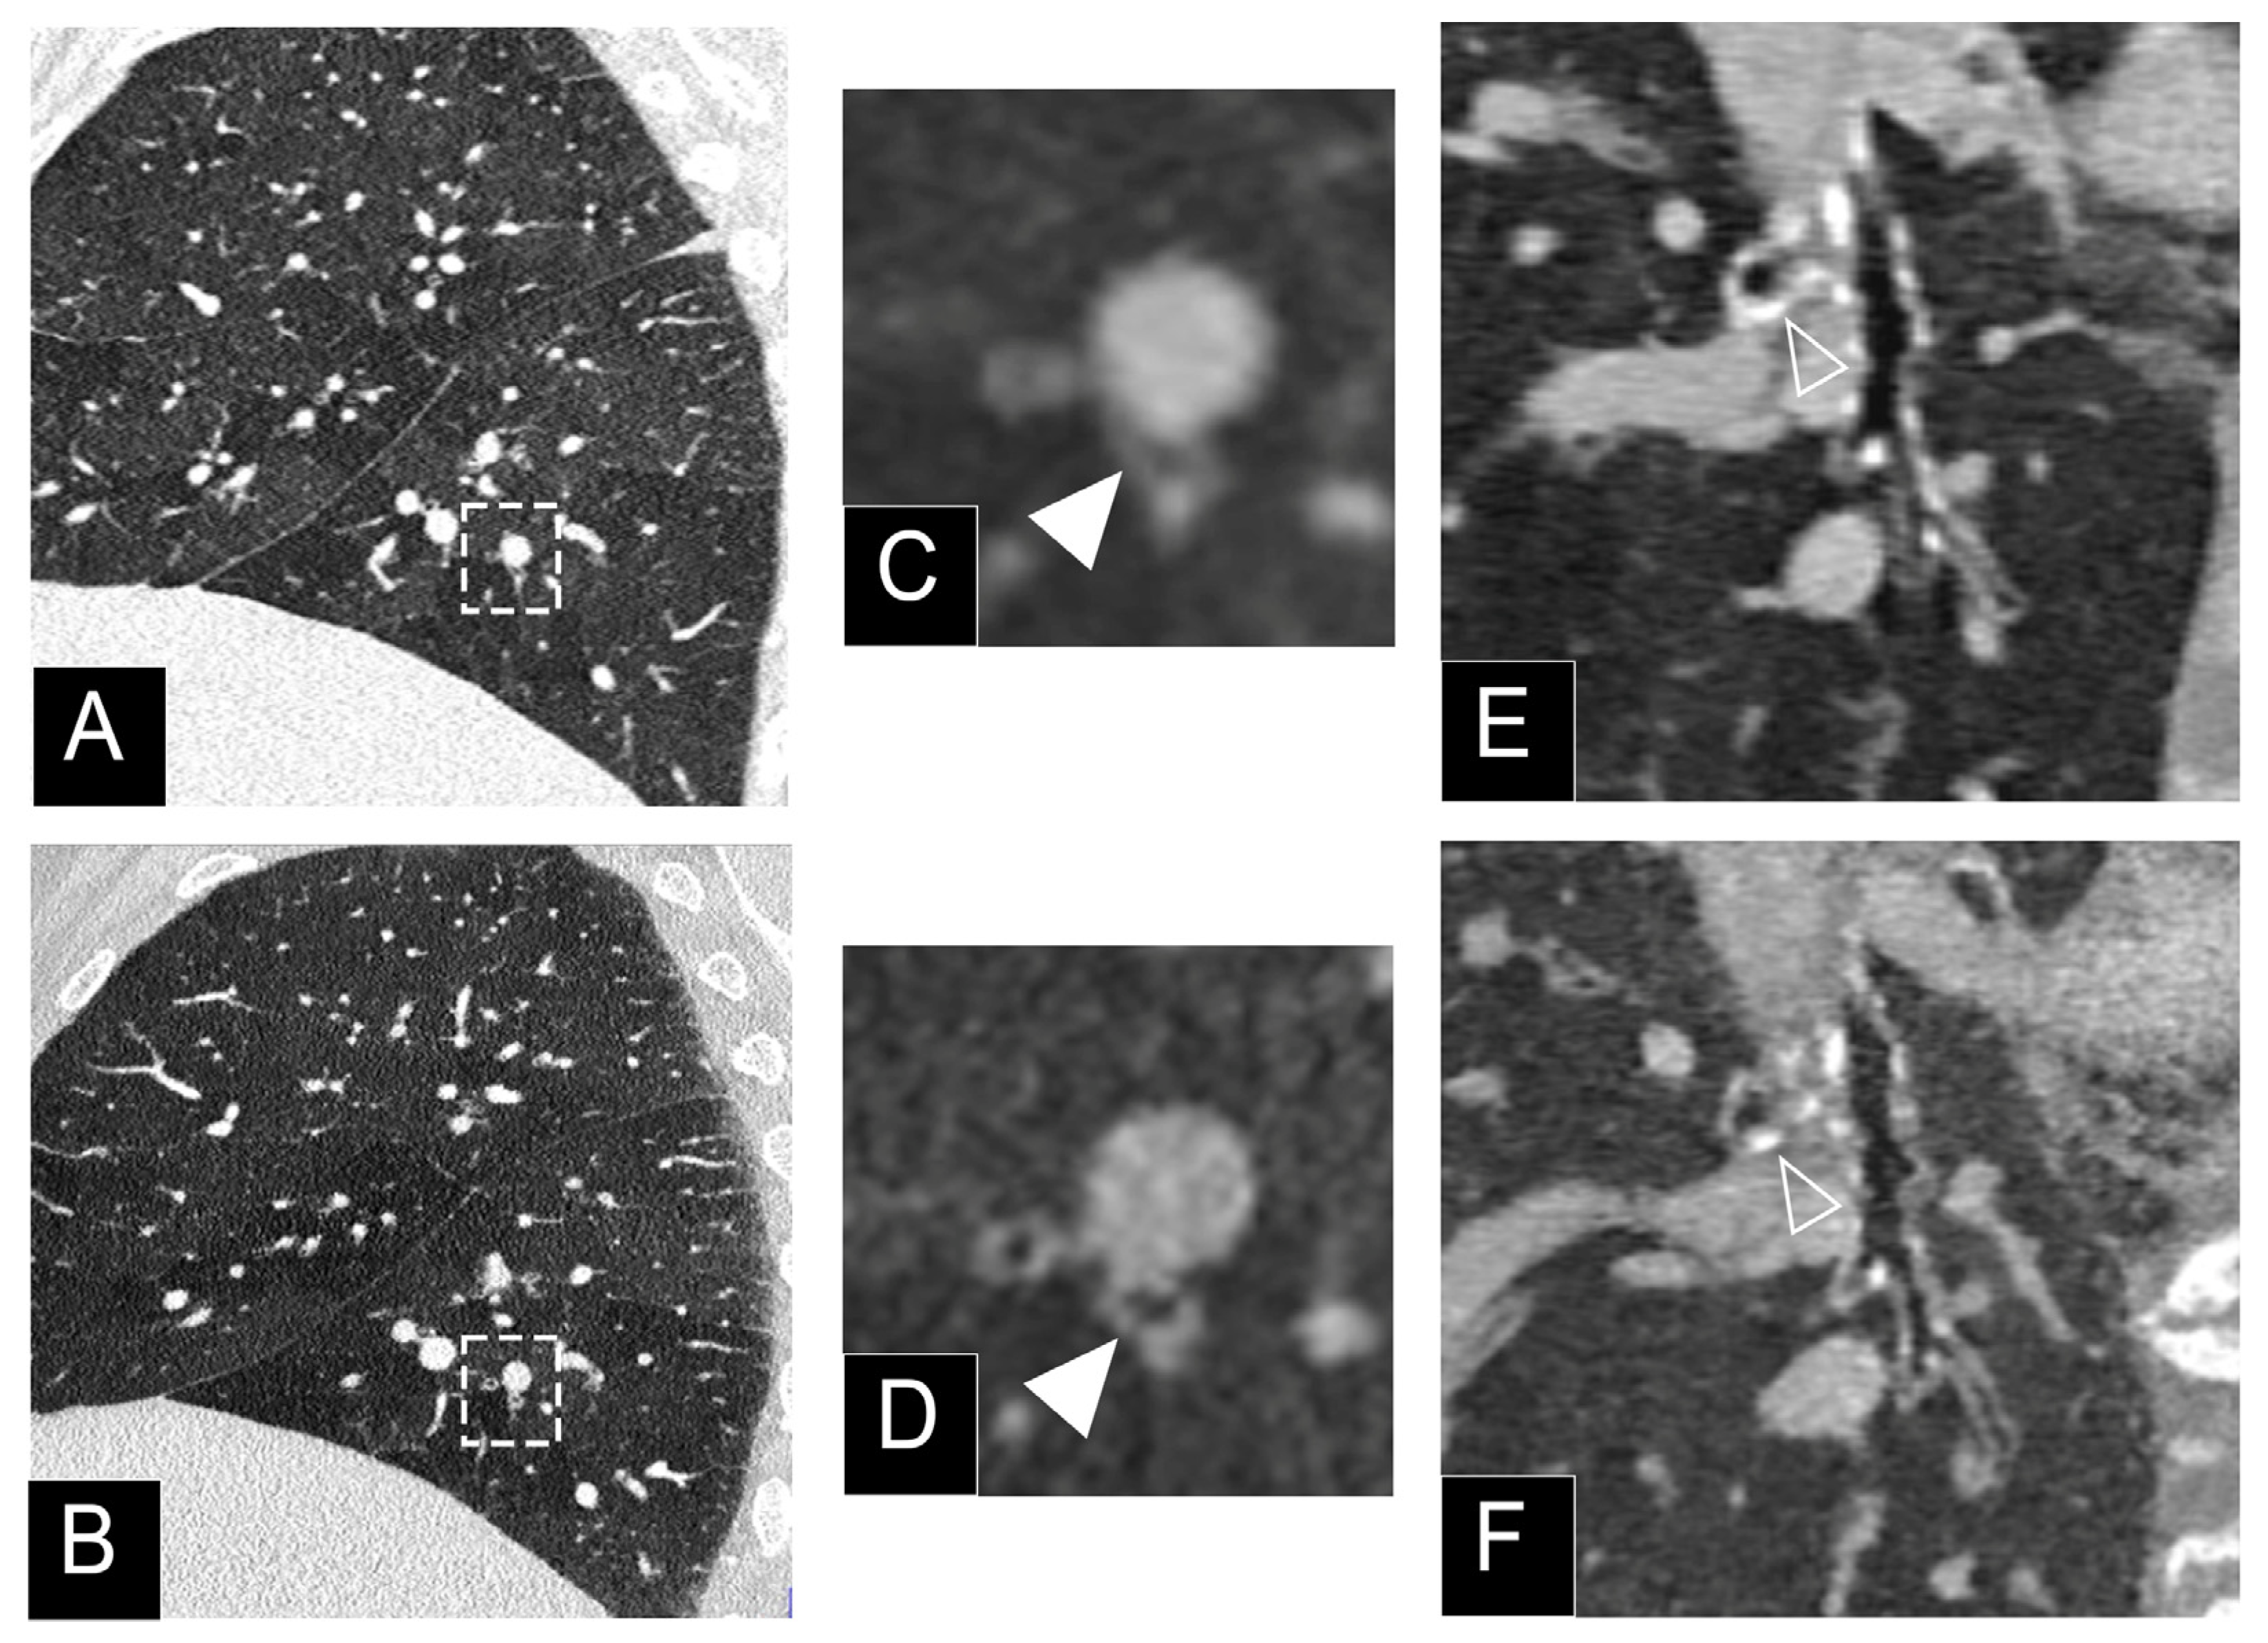

3.2. Nodule Imaging

- Si-Mohamed, S.A.; Greffier, J.; Miailhes, J.; Boccalini, S.; Rodesch, P.A.; Vuillod, A.; van der Werf, N.R.; Dabli, D.; Racine, D.; Rotzinger, D.; et al. Comparison of image quality between spectral photon-counting CT and dual-layer CT for the evaluation of lung nodules: A phantom study. Eur. Rad. 2021, in press. [Google Scholar] [CrossRef] [PubMed]